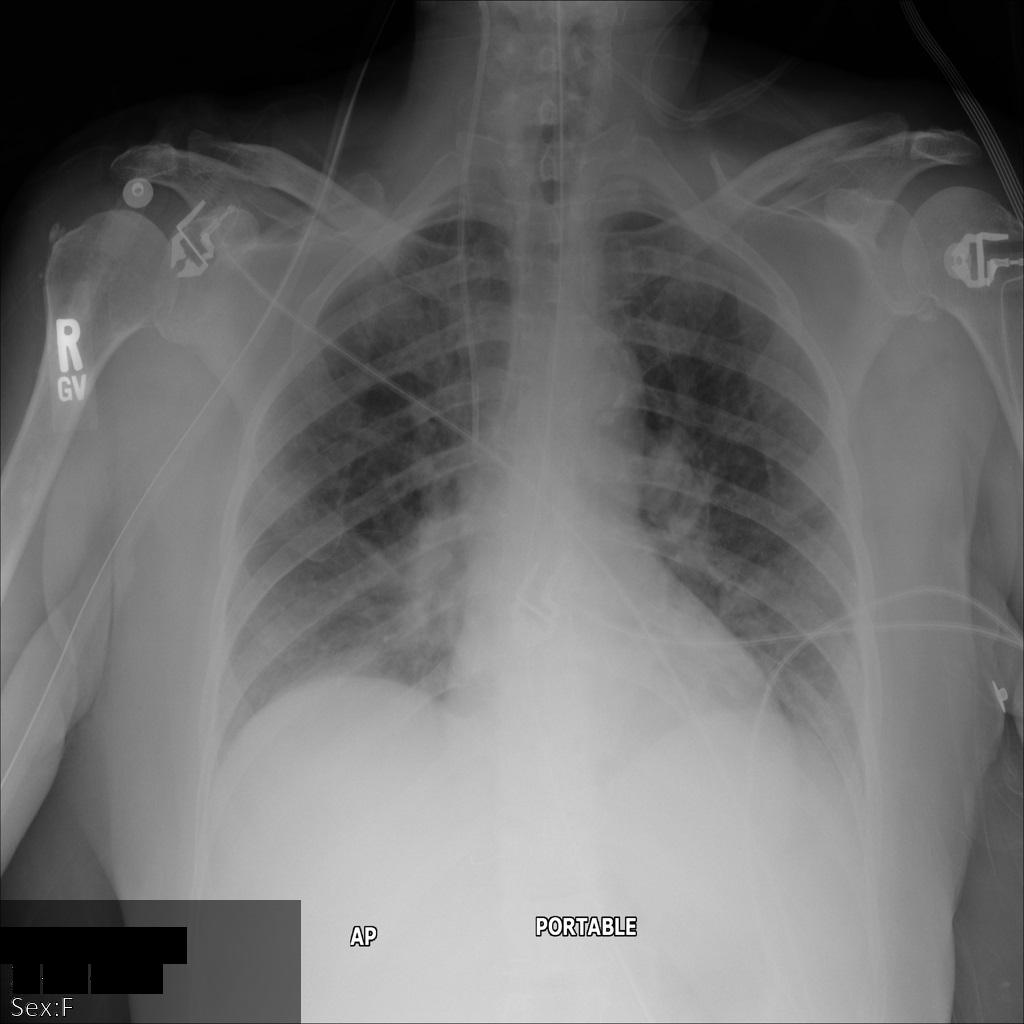

Chacune des sections suivantes fournit des exemples d'anonymisation de données DICOM à l'aide de différentes méthodes. Une sortie de l'image anonymisée est fournie avec chaque échantillon. Chaque exemple utilise l'image d'origine suivante comme entrée :

xray_original

Vous pouvez comparer l'image de sortie de chaque opération d'anonymisation à cette image d'origine pour voir les effets de l'opération.

Une fois l'image envoyée à l'API Cloud Healthcare, elle apparaît comme suit. Alors que les métadonnées affichées dans les angles supérieurs de l'image ont été masquées, les informations de santé protégées qui sont incluses dans l'angle inférieur de l'image sont conservées. Pour supprimer également le texte incrusté, consultez la section Masquer le texte incrusté dans les images.

dicom_keeplist